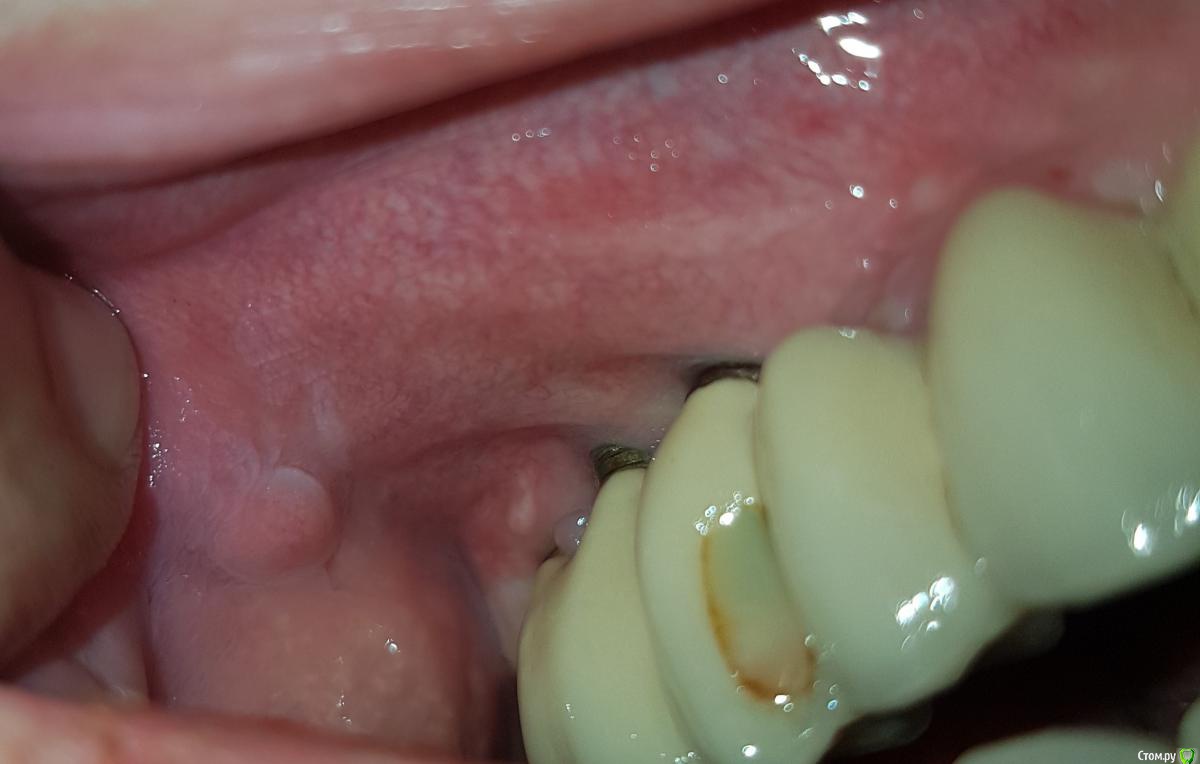

Чеширский Кот Опубликовано 25 декабря, 2019 Автор Поделиться Опубликовано 25 декабря, 2019 Срез малоинформативный, но, на первый взгляд, явных проблем с имплантами нет. Смущает вид конструкции, теоретически это может привести со временем к перегрузке, но это уже в ветку ортопедии вопрос. Прыщик сфотографировать бы, ну и можно попробовать у каждого имплантата срезы отскриншотить, но без очного осмотра с Вашим анамнезом и тем, что показывают снимки, скорее всего причину болей не выявитьСпасибо за ответ. Я понимаю, что осмотр в живую даст более информативный ответ, но все же вдруг на расстоянии что-то получится выявить. Фото больного места прикреплен. Как это сделать, скрины срезов имплантов? Спасибо за мнение о виде конструкции, приму к сведению Ссылка на комментарий

Irouil Опубликовано 25 декабря, 2019 Поделиться Опубликовано 25 декабря, 2019 Вокруг имплантатов нет плотной слизистой, со временем это может привести к нежелательным дегенеративных процессах в тканях. Я бы рекомендовал консультацию пародонтолога, возможно потребуется снять конструкцию (она должна откручиваться), провести пересадку плотной десны с неба. Криминала не видно, но действовать надо Ссылка на комментарий

Чеширский Кот Опубликовано 25 декабря, 2019 Автор Поделиться Опубликовано 25 декабря, 2019 (изменено) Вокруг имплантатов нет плотной слизистой, со временем это может привести к нежелательным дегенеративных процессах в тканях. Я бы рекомендовал консультацию пародонтолога, возможно потребуется снять конструкцию (она должна откручиваться), провести пересадку плотной десны с неба. Криминала не видно, но действовать надоА вот эти прыщики? Есть предположения? Возможен стоматит, отсюда и боли в десне? После НГ пойду по врачам на более тщательный осмотр и консультацию. Или затягивать на три недели не стоит? Изменено 25 декабря, 2019 пользователем Чеширский Кот Ссылка на комментарий